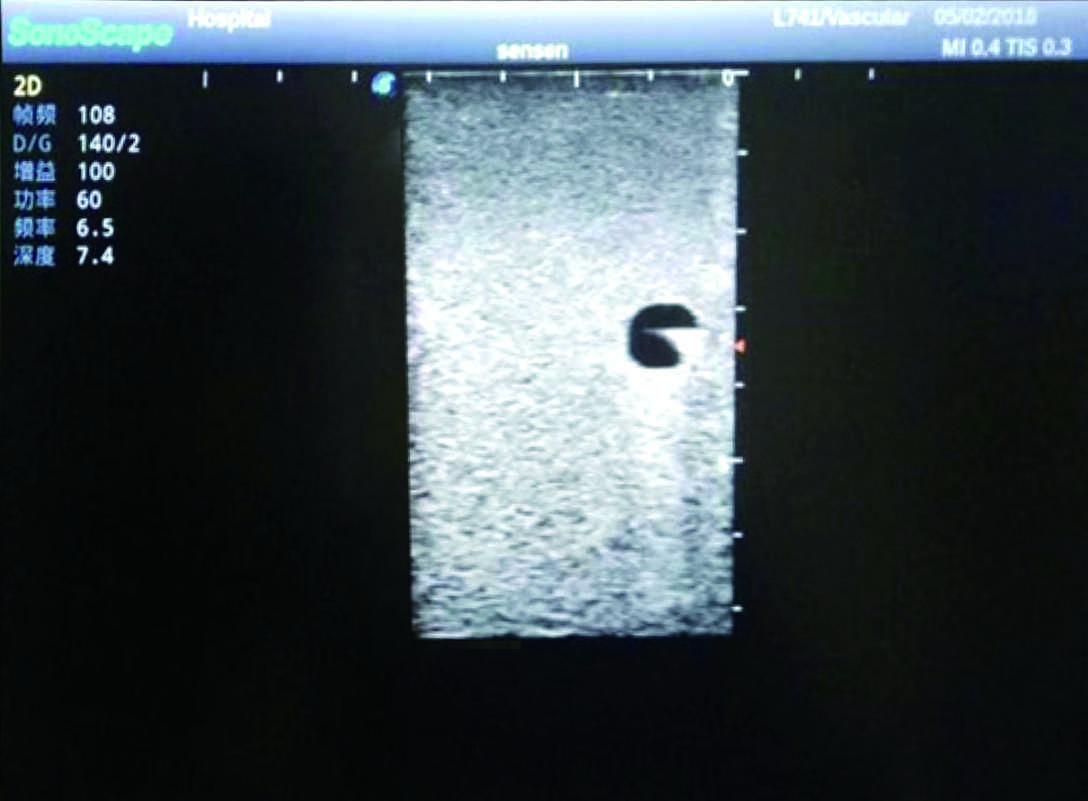

Model TYE1510.1

Product size(mm) 700×500×160

It is a model covering up from lobulus auriculae plane to the umbilical plane, and it has anatomical structures like clavicle, rib, sternocleidomastoid, jugular vein and basilic vein.

1)   Made of high molecular polymer ultrasound material, close to the real skin

2)   It can be used by real ultrasound machines

3)   Clear and real images of the tissues and organs (basilic vein and superior vena cava)

4)   When conducting vascular puncture, the piercing can be truly felt, and venous blood outflow can be seen

5)   Observe the guide wire marches

6)   Detect whether the catheter is properly placed